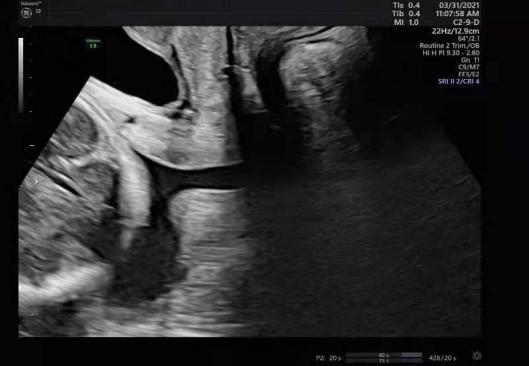

4月9日,已怀孕23周+的李女士,与家人来到龙华区妇幼保健院进行例行的超声波检查,即将到来的新生命让他们脸上满是期待和笑容,但检查结果却令人大吃一惊。

检查中,超声医生常规查看宫颈口,却发现李女士的宫颈口已经扩张成U型,部分羊膜囊已突出宫颈外口,羊膜囊就是装娃的那个大水袋,羊膜囊突出就意味着:本来在子宫里住着的娃,随时可能掉出来!